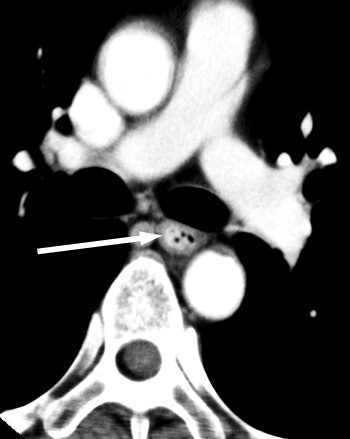

![]() |

| The arterial phase image of 64-year-old male with T3 esophageal cancer. In this case, the tumor is visualized as "wall thickening." The muscle layer cannot be seen. |

"In the atrial contraction period, we could observe a low-density band between the left atrium and the (esophageal cancer), but it was undetectable in the end-systolic phase," he said. "The low-density band between the (left atrium) and the (esophageal cancer) in the 70% to 80% portions of the RR interval could be visualized in all 12 subjects; however, it was not visualized in the 40% portion in any of the subjects."

"The left atrium contracts separately from the esophageal cancer, and we concluded that the tumor does not invade the left atrium," Shuto said. "(The case was) diagnosed as T3. All 12 subjects underwent esophagectomy, and all revealed squamous cell carcinomas. No one had evidence of esophageal cancer invasion of the left atrium in histological findings."

Thus, the negative predictive value was 100% for identifying pericardial invasion. "We predicted if a low-density band between left atrium and the esophageal cancer is visualized, the tumor will be stage T3 cancer.... ECG-gated multislice CT can reduce the influence of cardiac pulsation," he concluded.